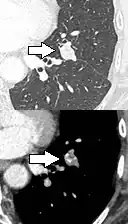

- Margin morphology: a spiculated margin is a risk factor for cancer.[8] Benign causes tend to have a well defined border, whereas lobulated lesions or those with an irregular margin extending into the neighbouring tissue tend to be malignant.[10] In particular, spiculations are highly predictive of malignancy with a positive predictive value up to 90%.[9] Also, a "notch sign", which is an abrupt indentation of the nodule, increases the risk of cancer, but may also be found in granulomatous diseases.[9]

-

subpleural nodule.[9] -

Round well-delineated solid lung nodule with smooth border.[9] -

Lobulated nodule.[9] -

Spiculated lung nodule.[9] -

A "notch sign".[9] -

A triangular perifissural node can be diagnosed as a benign lymph node.[9]